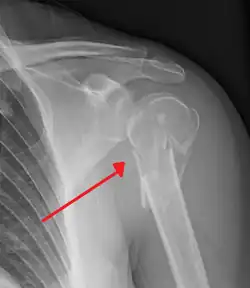

Surgical neck

The surgical neck is a narrow area distal to the tubercles that is a common site of fracture. It makes contact with the axillary nerve and the posterior humeral circumflex artery.

The axillary nerve is located at the proximal end, against the shoulder girdle. Dislocation of the humerus's glenohumeral joint has the potential to injure the axillary nerve or the axillary artery. Signs and symptoms of this dislocation include a loss of the normal shoulder contour and a palpable depression under the acromion.